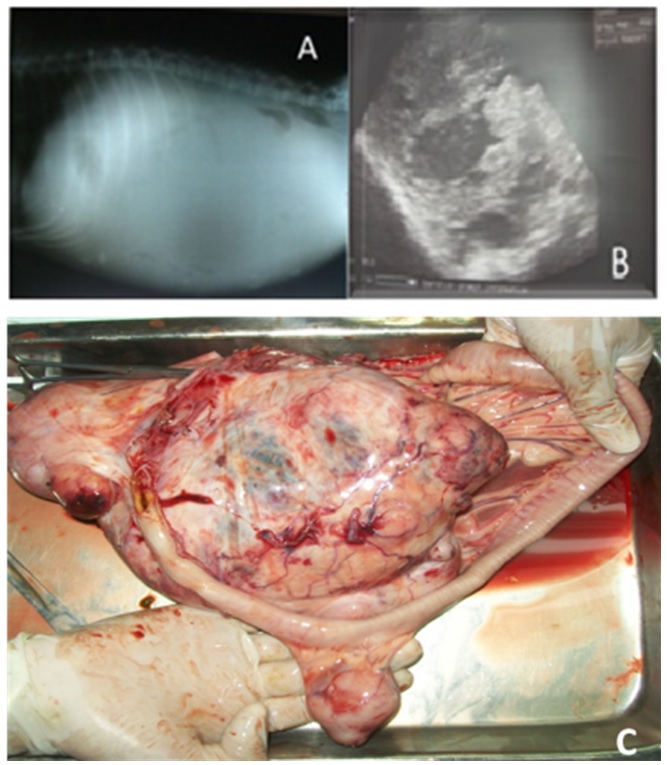

Una radiografía abdominal con proyección laterolateral del abdomen se realizó, mostrando radio opacidad generalizada y evidenciando la presencia de líquido en el abdomen (Figura 1A). Mediante ultrasonografía abdominal se observaron áreas anecóicas en la masa abdominal (Figura 1B), lo que sugería contenido liquido dentro del tumor, sin embargo, al examen no se pudo determinar en qué estructura se ubicaba la masa. Se realizó una laparotomía exploratoria, que reveló la ubicación de la masa, unida al mesenterio del intestino delgado. El paciente falleció al intentar retirar la masa debido a una hemorragia severa.

Hallazgos patológicos. El canino fue tomado para necropsia. Se extrajo una masa tumoral que fue firme con superficie irregular. Medía unos 18 cm de largo por 13 cm de ancho (Figura 1C). Los ganglios linfáticos estaban edematosos. Se observó una gran vascularización tumoral, con un contenido sanguinolento no coagulado. Cuando se incidió la masa pareció tener una consistencia irregular.